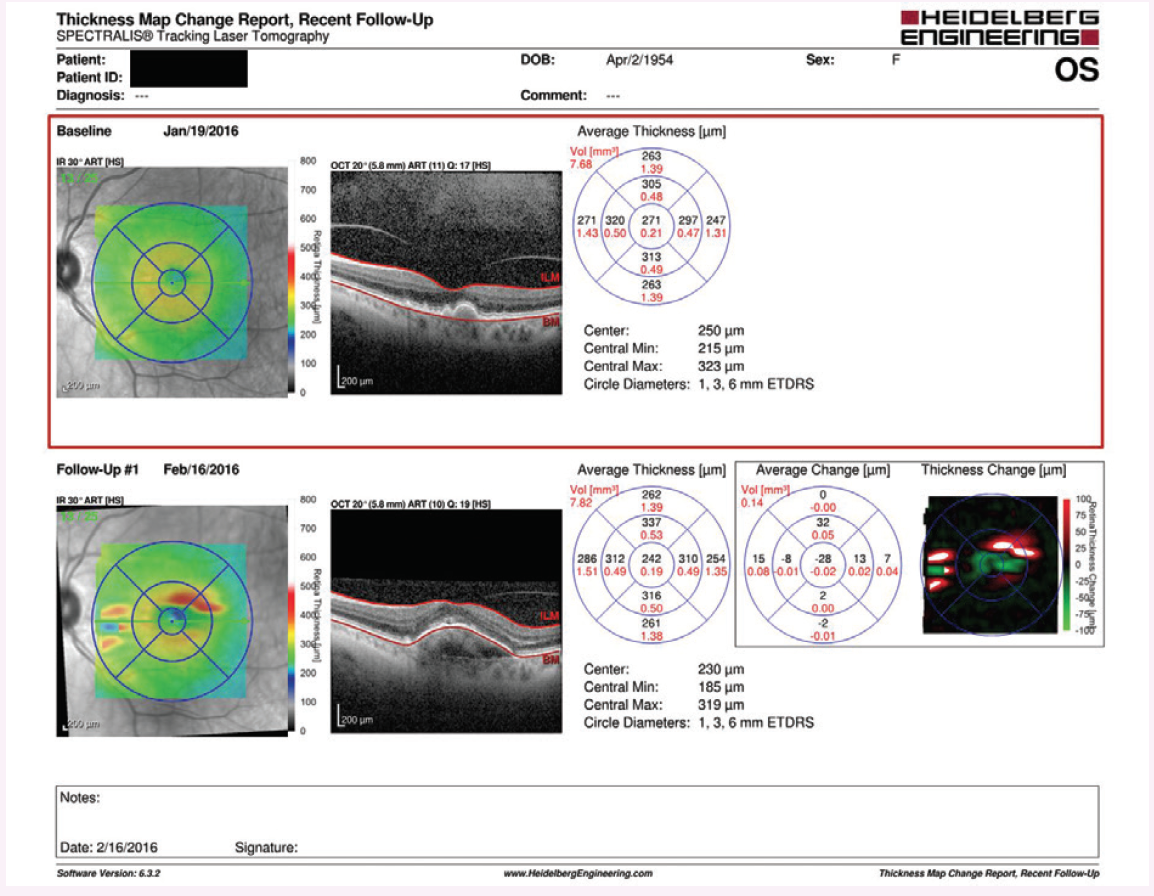

Early in my use of the mVT service, a 68-year-old patient with dry AMD was referred to me. She was asymptomatic, with 20/50 visual acuity in each eye. Fundus examination and spectral-domain optical coherence tomography (SD-OCT) showed intermediate and large drusen without CNV or exudation (Figure 2). The patient owned both an iPhone and an iPad. I discussed testing with a standard Amsler grid versus using the mVT app, and she was immediately interested in the latter option. I sent her home with the instruction to use the app two to three times per week, and I scheduled her to see me again in 6 months.

Figure 2. Asymptomatic 68-year-old patient with dry AMD. Fundus examination and SD-OCT at baseline showed intermediate and large drusen without CNV or exudation.

Figure 3. After 4 weeks of home monitoring, the mVT app detected a worsening in vision. A large pigment epithelial detachment with subretinal fluid were observed on SD-OCT.

To my surprise, I received an alert signaling a worsening in this patient’s testing just 4 weeks later. She came in the next day, and my examination and SD-OCT showed a large pigment epithelial detachment with subretinal fluid (Figure 3). Her visual acuity had decreased to 20/60, and she reported a small change in vision, but she had attributed it to a change in her eyeglass prescription. The patient reported that, if it were not for the mVT app, she would not have made an appointment to come in as a result of the change in vision.